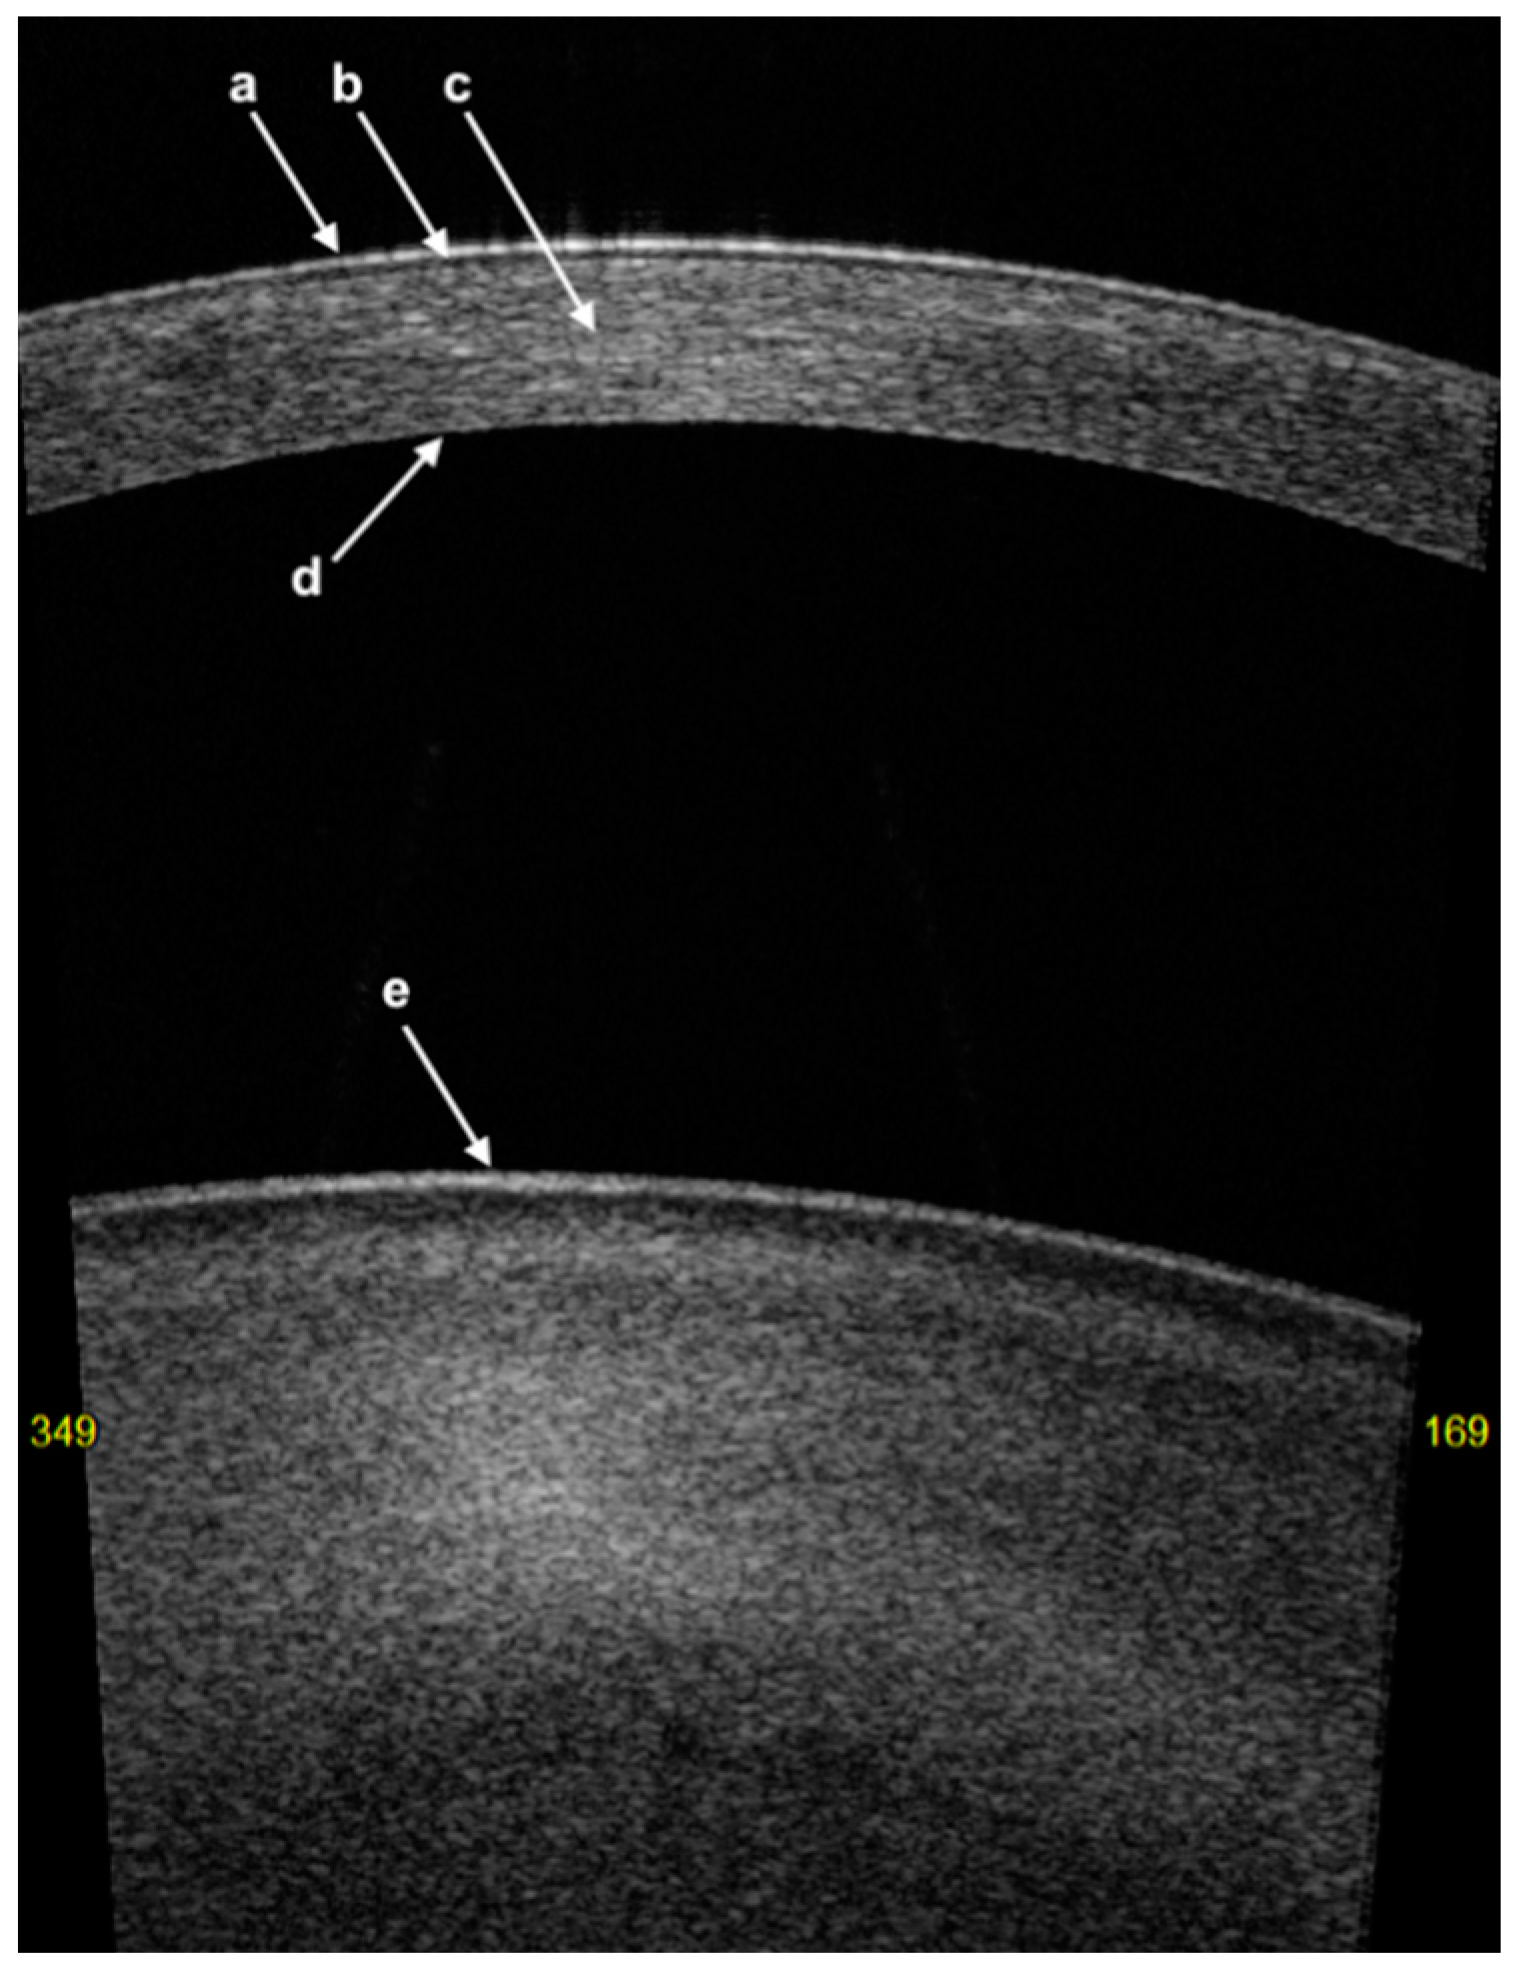

3. Corneal Anatomy on AS-OCT Imaging

- The first hyper-reflective band represents the tear film with a thickness of less than 5 µm [24];

- The first hyporeflective band represents the cornea epithelium with a thickness of between 50 and 70 µm;

- Bowman’s layer (BL) is represented as a linear structure with similar hyper-reflectivity to that of the stroma;

- The stroma has variable hyper-reflectivity with a thickness of around 500 µm;

- The pre-Descemet’s layer (or Dua’s layer (PDL)) and Descemet membrane (DM) are shown as a hyper-reflective band of tissue. In the context of DM detachment (type 2 or mixed), PDL and DM may show as two separate hyper-reflective bands [25].